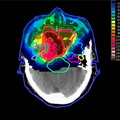

- Формирование очень тонкого протонного луча – фокусировка выполняется с помощью электромагнитного поля и позволяет фокусировать луч непосредственно на опухоли, даже незначительных размеров, без повреждающего действия на окружающие здоровые ткани головного мозга.

- Эффект пика Брегга – заключается в высвобождении энергии протонами строго на заданной глубине их прохождения. Этот эффект присущ только протонному лучу и отсутствует в других видах излучения (рентгеновском или ионизирующем). Такая ключевая особенность является показанием к применению протонной терапии при раке мозга, так как нет повреждающего воздействия на здоровые ткани, лежащие перед опухолью и за ней.